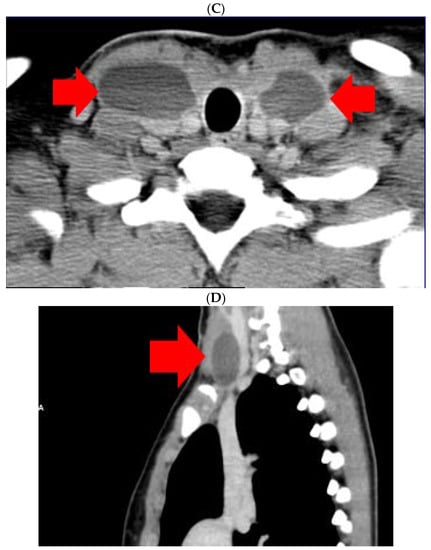

- Touska, P.; A Constantinides, V.; Palazzo, F.F. A rare complication: Lymphocele following a re-operative right thyroid lobectomy for multinodular goitre. BMJ Case Rep. 2012, 2012, bcr0220125747. [Google Scholar] [CrossRef] [PubMed]

- Ohta, N.; Fukase, S.; Suzuki, Y.; Ishida, A.; Aoyagi, M. Treatments of various otolaryngological cystic diseases by OK-4321: Its in-dications and limitations. Laryngoscope 2010, 120, 2193–2196. [Google Scholar] [CrossRef] [PubMed]